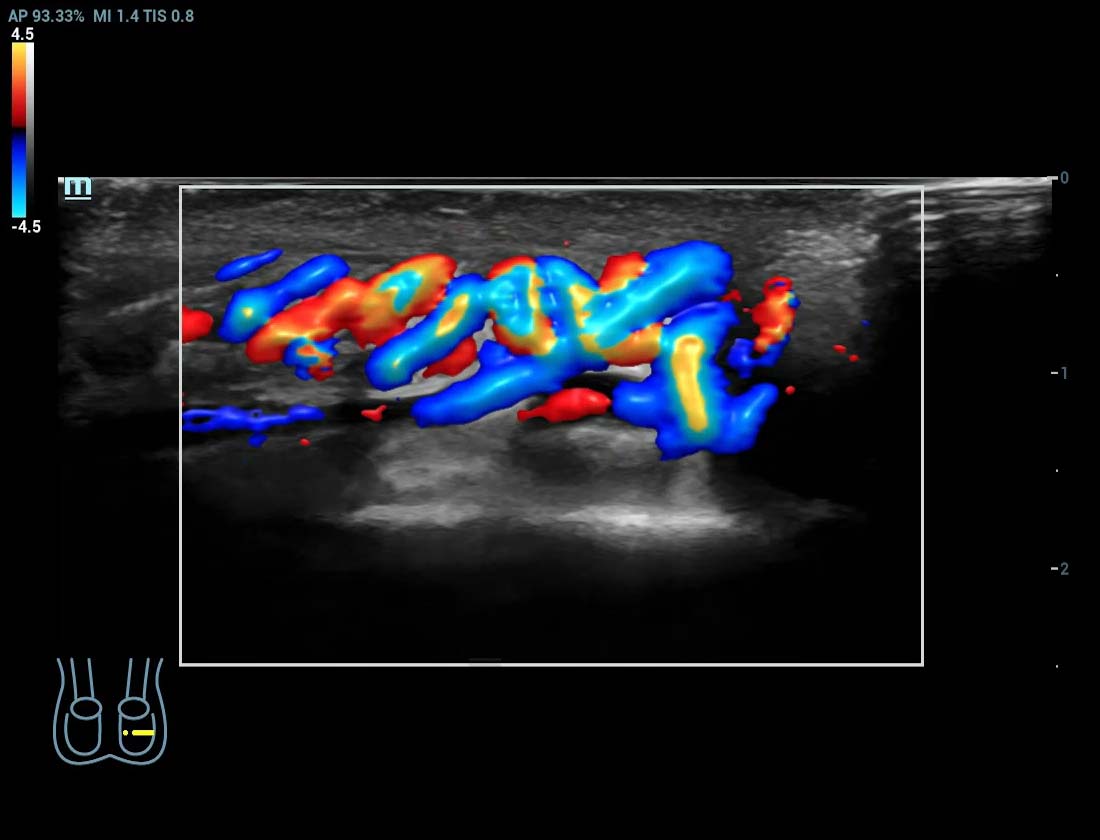

Glazing Flow varicocele

Ultra Micro Angiography (UMA)

UMA migliora la sicurezza diagnostica ampliando la visibilitĂ dei flussi sanguigni fino al livello dei vasi piĂč piccoli, con una sensibilitĂ e una risoluzione superiori.

Rene sUMA

Massa mammaria pUMA

Tumore alla tiroide sUMA